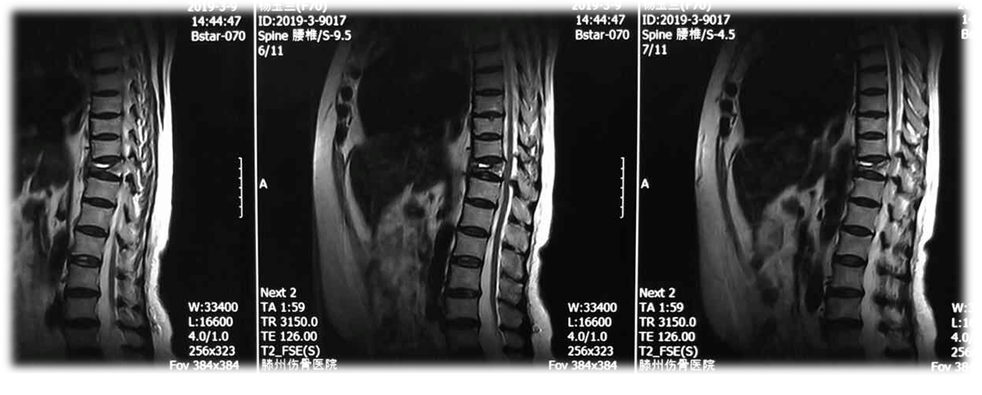

术前MRI

术后2周MRI

术前

术后2周